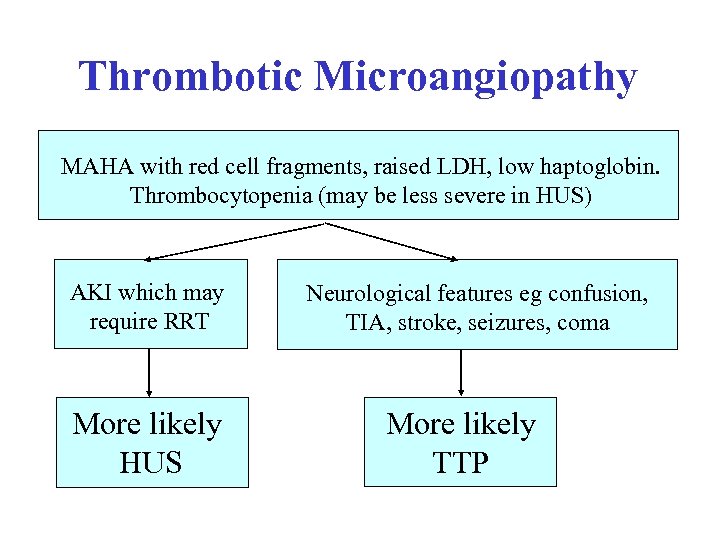

Thrombotic Microangiopathy MAHA with red cell fragments, raised LDH, low haptoglobin. Thrombocytopenia (may be less severe in HUS) AKI which may require RRT More likely HUS Neurological features eg confusion, TIA, stroke, seizures, coma More likely TTP

Thrombotic Microangiopathy MAHA with red cell fragments, raised LDH, low haptoglobin. Thrombocytopenia (may be less severe in HUS) AKI which may require RRT More likely HUS Neurological features eg confusion, TIA, stroke, seizures, coma More likely TTP